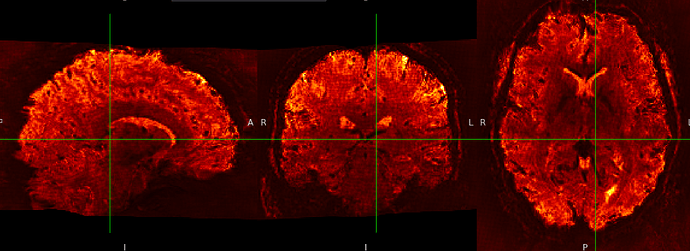

SE sequence in MNI152NLin6Asym-res1

The checkerboard pattern is more evident in the ME sequence where it is also visible outside the brain, but it is present in both, ME and SE inside the brain.